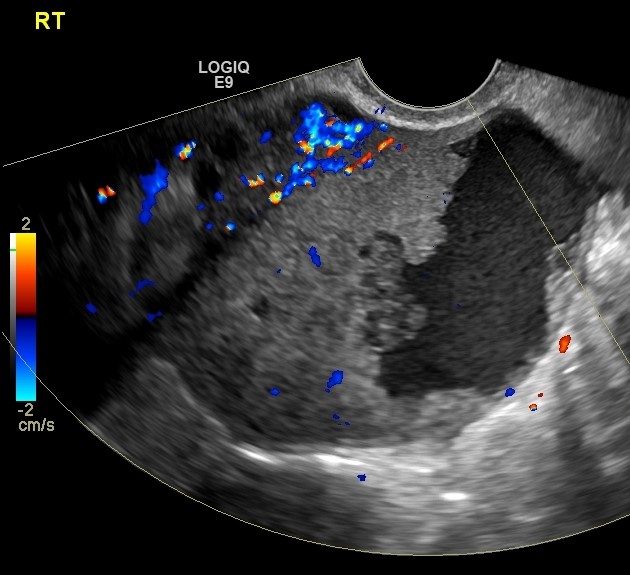

КТ диагностика тубоовариального абсцесса: Подходы и изображения

Раздел: Объективный взгляд